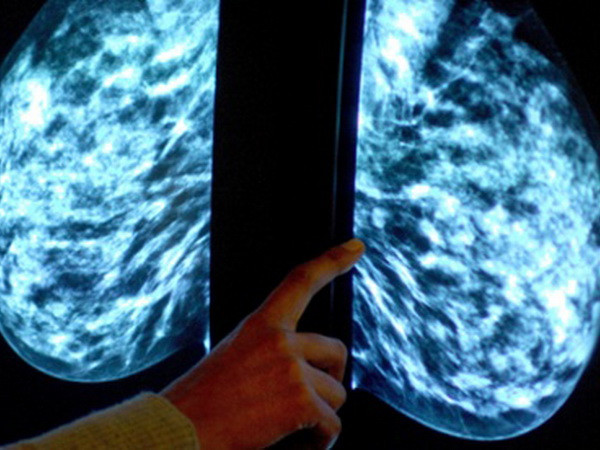

New Zealand công bố kế hoạch quốc gia về phòng chống ung thư ảnh 1Ảnh minh họa. (Nguồn: PA)